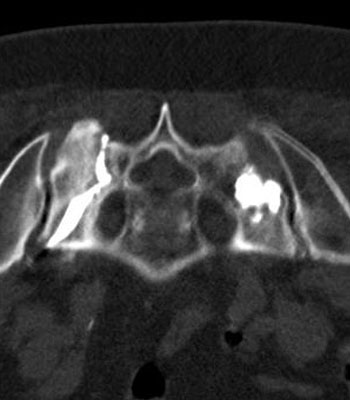

Die (gutartige) Vergrößerung der Prostata (Prostatahyperplasie) führt bei vielen Männern ab etwa dem 50.Lebensjahr zu einer Einengung der Harnröhre mit zunehmenden Problemen beim Wasserlösen. Die interventionelle Radiologie bietet bei Beschwerden, die medikamentös nicht gelindert werden können, eine minimal-invasive Prostataembolisation (PAE) an. Die Methode wird in enger interdisziplinärer Zusammenarbeit mit Urologen seit mehreren Jahren auch in Wien angeboten. Ähnlich wie bei Myomen ist die Prostataembolisation eine minimal-invasive und schonende Therapie, benötigt keine Allgemeinnarkose und ist mit einem kurzen Krankenhausaufenthalt verbunden. Nach lokaler Betäubung wird über die Leistenarterie ein dünner Schlauch (Katheter) in die Arterie der Prostatadrüse eingeführt, anschließend werden winzige Kügelchen bis zum Verschluss der zentralen Anteile der Arterien langsam injiziert. So bewirkt die Embolisation mittelfristig ein Schrumpfen der Prostatadrüse. Oft stellt sich bereits kurz nach der Embolisation eine für den Patienten merkbare Besserung der Beschwerden ein.

-

Prostataarterie links

nach Embolisation links

Prostataarterie rechts

nach Embolisation rechts